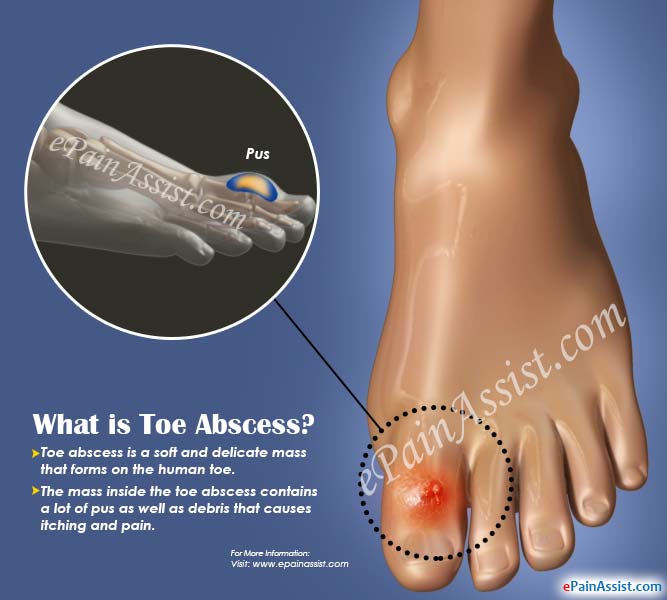

What is Toe Abscess|Causes|Symptoms|Treatment|Home Remedies|Prognosis …